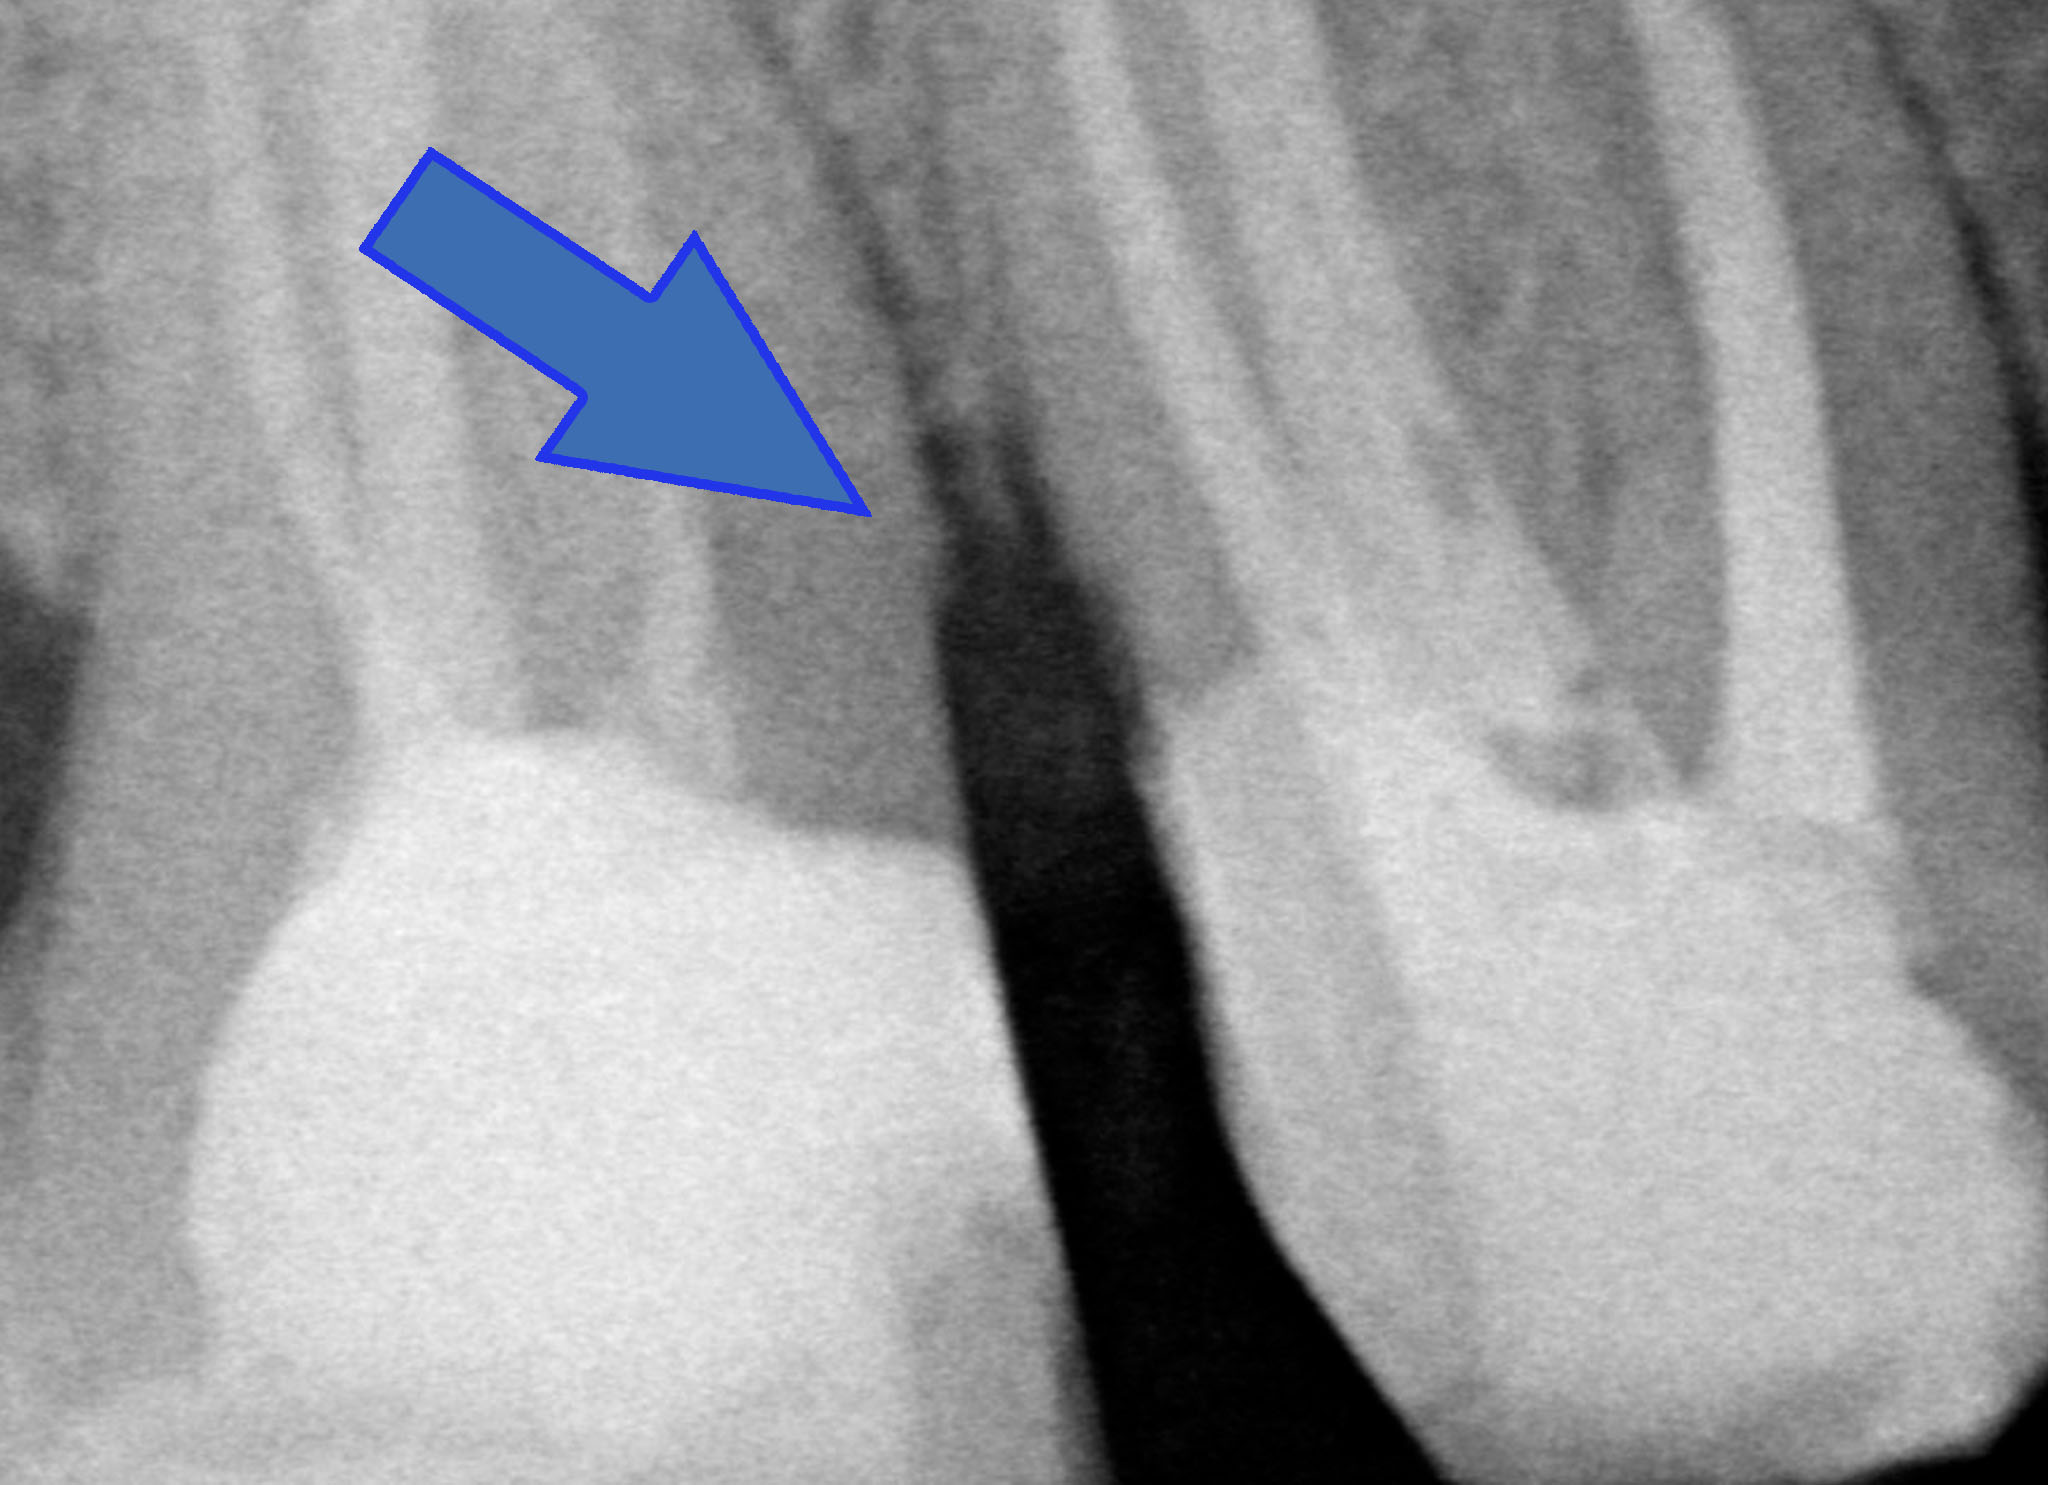

“Hei hei guarda un po’ lì cosa ha combinato questo?! Una tacca sul dente dietro!!”

Allungamento di corona clinica 005

Beh caro amico, la fresa tra i due denti ci deve passare e se le due radici sono troppo vicine bisogna creare lo spazio per una papilla interdentale sana e non sofferente, dove poter mettere un filo retrattore (anzi due) alla presa dell’impronta. Quindi sì, lo ammetto: una tacca di qua e una tacca di là!

PS: l’allungamento di corona clinica non vuol dire aprire la papilla fresare un po’ di osso interprossimale e chiudere! Quello tecnicamente si chiama creare un difetto parodontale iatrogeno.